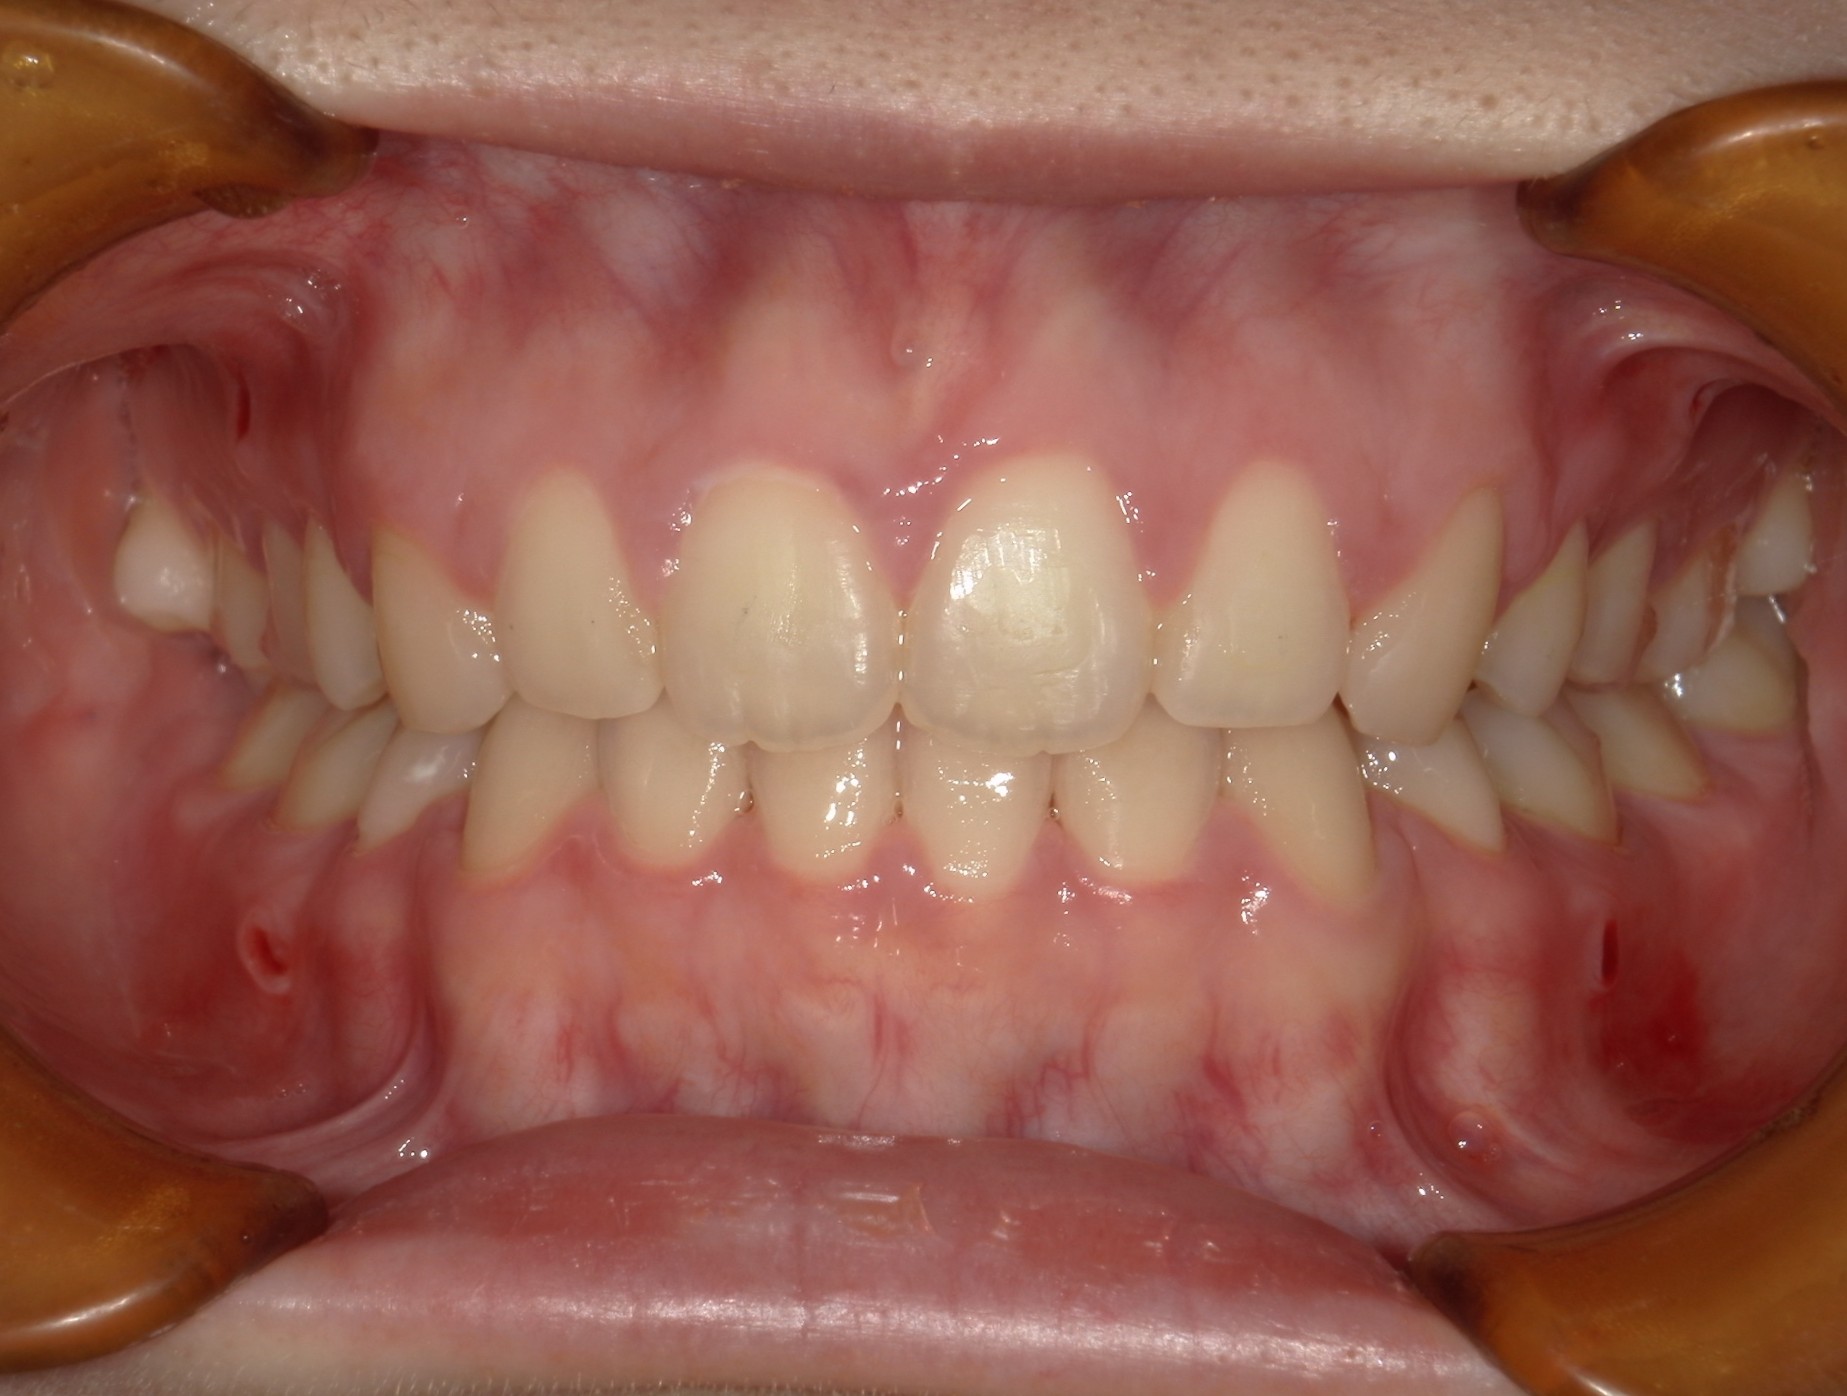

口内正面

治療前

治療後

上の前歯に重なりがあることと口元が前突していることが問題となっていました。

上の前歯は唇側に傾斜しており、全体的に手前に倒れるような歯の配置となっていました

検査の結果、傾斜を治し、口元を内側に引き込むため、上下の歯を抜いてワイヤー装置で歯を並べることとしました

抜歯によって得られたスペースを十分に活かすことで、上の前歯の重なりと、口元の前突感、全体的な歯の傾斜を改善することが出来ました。